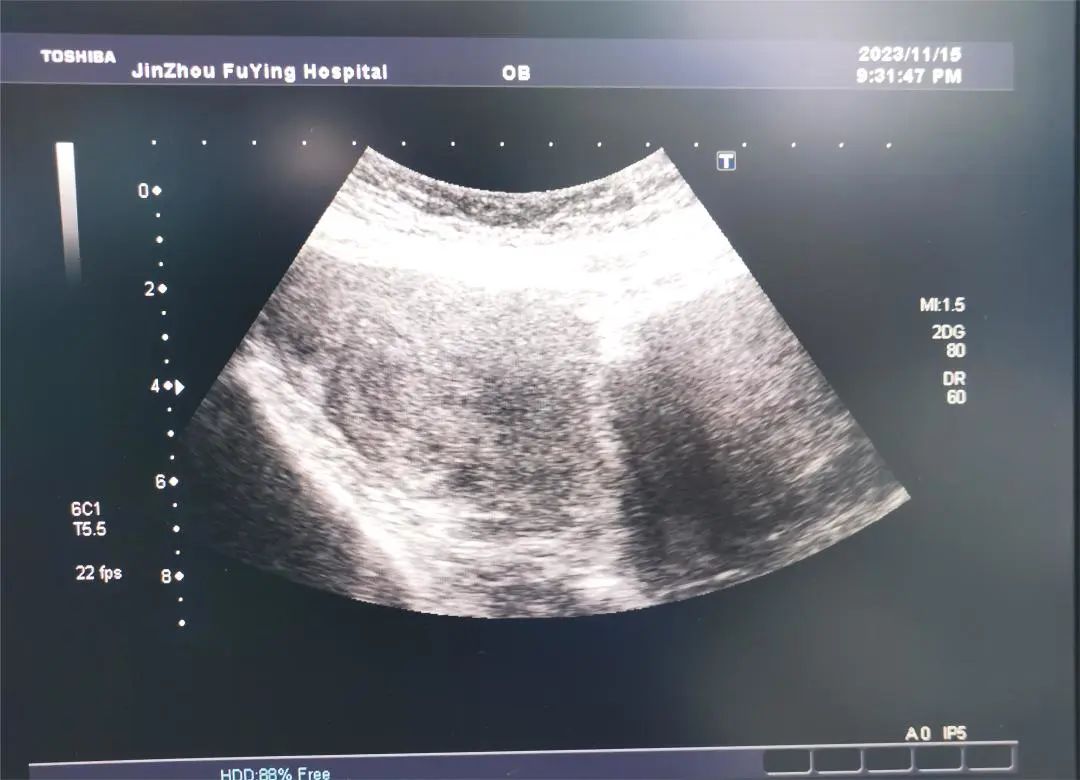

11月16日,计划生育科来了一位特殊的手术患者。该患者3天前在当地医院就诊要求行人工流产手术,因术前超声检查提示“巨大子宫颈肌瘤“,当地医院考虑手术困难,被拒绝手术,遂来我科诊治。

门诊医生详细询问患者病史,“患者妊娠8周”,内诊宫颈前壁可触及约7.0×5.0cm肿物,宫颈被压迫变形,评估手术难度大,引起我科高度重视;人流手术室金医生在看到病志后,再次对患者病情进行评估,巨大子宫颈肌瘤压迫宫颈导致宫颈管变形、狭窄可能带来的一系列风险,如进入宫腔困难等,在术前请超声科会诊并对术中可能发生的情况进行讨论后,向患者及家属详细交代病情、讲解手术的难度及风险。经过医生与患者及家属的反复交代沟通后,在患者及家属的信任与期待中,手术平稳有序的开始了……